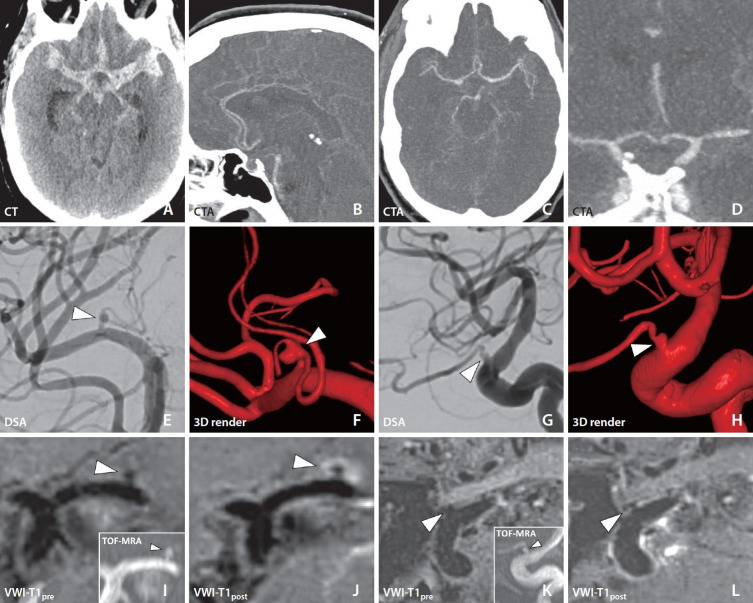

A patient presented with acute onset headache and subsequent unconsciousness. The neurologic exam showed left-sided myoclonic jerking and right flaccid hemiparalysis. Noncontrast computed tomography revealed diffuse subarachnoid hemorrhage (SAH) with acute hydrocephalus. Initial digital subtraction angiography (DSA) showed no culprit source for SAH. Repeat DSA on day 7 after initial presentation raised suspicion for left internal carotid artery ophthalmic segment and left lateral lenticulostriate artery (LSA) aneurysms. A magnetic resonance vessel wall imaging (VWI) exam was performed given the presence of multiple potential culprit aneurysms. Vessel wall enhancement around the dome of the left LSA aneurysm suggested rupture, which then facilitated treatment with surgical clipping. LSA aneurysms are exceedingly rare and challenging to treat. Given the associated high degree of morbidity, expedient diagnosis is critical to direct management. VWI could be a valuable tool for detecting ruptured aneurysms in the setting of angiogram-negative SAH.